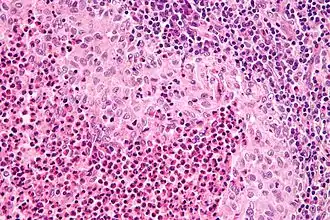

Células de Langerhans são células abundantes na epiderme, contendo grânulos de Birbeck. Elas estão normalmente presente em linfonodos, podendo ser encontradas em outros órgãos na condição de histiocitose e são uma das responsáveis pelo controle das respostas imunológicas da pele.

São células móveis e dendríticas responsáveis pela imunovigilância cutânea. Têm a função de captar, processar e apresentar os antígenos aos linfócitos T. Representam 3–6% de todas as células epidérmicas. Contém um marcador citoplasmático específico, os grânulos de Birbeck, que se originam do processo de endocitose. Na microscopia de luz as células de Langerhans podem ser demonstradas por técnicas histoenzimáticas como a ATPase e especialmente pela imunoistoquímica através do marcador CD1a.